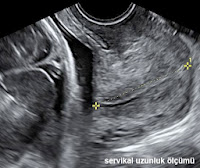

HAMİLELİKTE RAHİM AĞZI UZUNLUĞU

Serviks (rahim ağzı) boyu servikal kanalın internal osu ile eksternal osu arasındaki uzunluktur. Hamilelikte servikal uzunluk ultrason ile belirlenebilmektedir.. Serviks boyu hamilelikte ileriki aylarda olabilecek preterm eylem (erken doğum) riskini öngörmede veya preterm eylem tehtidi tanısı konan hastada doğum riskinin yüksekliğini belirlemede kullanılabilir.

Servikal uzunluk ölçümü nasıl yapılmalıdır?

- Bütün endoservikal kanal izlenebilecek şekilde sagittal görüntü elde edilmelidir.

- Görüntü serviksin ekranın en az 2/3'ünü kaplayacağı kadar büyütülmelidir.

- İnternel ostan ekternal osa kadar servikal kanal boyunca uzunluk ölçülmelidir.

- En az 3 ölçüm yapılarak en kısa olan kaydedilmelidir. Servikal veya uterin kontraksiyonlar nedeniyle ölçüm sırasında serviksin uzunluğunda ve şeklinde değişiklik gözlenebilir. Bu nedenle ölçüm en az 5 dakika sürecek şekilde yapılmalıdır ve en kısa ölçüm kaydedilmelidir.